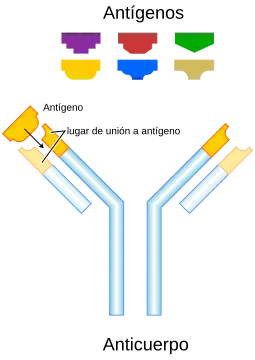

Lo característico de la patogenia del LES es la respuesta inmune dirigida contra los antígenos nucleares endógenos. Los autoantígenos liberados por células apoptóticas son presentados por las células dendríticas a los linfocitos T iniciando su activación. Estos linfocitos interactúan mediante citocinas como la interleucina 10 e interleucina 23 y mediante moléculas de superficie como el CD40L y el CTLA-4, con los linfocitos B para que éstos produzcan los anticuerpos contra estos componentes propios (por lo tanto se producen autoanticuerpos). También existe un mecanismo de producción de autoanticuerpos por los linfocitos B, no mediada por linfocitos T, a través de señales de los receptores BCR (propios de los linfocitos B) y los receptores de tipo Toll o TLRs.[8]

- Células B y T: en el LES se produce un aumento notable del número de células circulantes secretoras de inmunoglobulinas —hasta 50 veces—, junto con una activación selectiva de las células B, dirigidas contra un número determinado de antígenos.[46] Las células T son importantes en la activación de las células B y en la posterior producción de autoanticuerpos. Aunque en el LES el número total de células T está disminuido, se ha observado en estos pacientes la presencia de células T hiperactivas específicas para autoantígenos.[46] También se han descrito múltiples anomalías de señalización, tanto en los linfocitos T como en los B, incluyendo hiperactividad e hiperreactividad celular.[21][47] La hiperreacción de las células T y B se traduce en una mayor expresión de determinadas moléculas, como HLA-D y CD40L, lo que demuestra que las células son activadas fácilmente por los antígenos que inducen las primeras señales activadoras y las moléculas que estimulan la activación celular completa a través de la segunda señal. El resultado final de estas anormalidades es la producción sostenida de autoanticuerpos patógenos y la formación de inmunocomplejos que se adhieren a ciertos tejidos.[48]

Los defectos en la depuración de células apoptóticas es una de las posibles explicaciones de ciertas enfermedades autoinmunes como el LES. - Autoanticuerpos: la producción de autoanticuerpos es un rasgo característico de los pacientes con LES. Su producción puede ser por activación policlonal de las células B o por estimulación inmune dirigida por autoantígenos.[47] Su importancia en el origen de la enfermedad se pone de manifiesto, por ejemplo, en el lupus eritematoso neonatal, que se piensa que es producido, al menos en parte, por el paso de los autoanticuerpos de la madre (anti-Ro y anti-La) al feto durante el embarazo, aunque también parece ser necesario un factor fetal complementario.[49] Además, los niveles del algunos autoanticuerpos llevan un curso paralelo a la actividad de la enfermedad y algunos se asocian con datos clínicos específicos de la enfermedad.[50]

- Autoanticuerpos e inmunocomplejos: los mediadores del LES son los autoanticuerpos y los inmunocomplejos que se forman con los antígenos. Los autoanticuerpos pueden estar presentes durante años antes de que aparezcan los primeros síntomas de la enfermedad.[51] Los autoantígenos que son reconocidos son presentados primariamente en la superficie de las células, particularmente por células activadas o bajo apoptosis, en las que los antígenos celulares han emigrado a la superficie celular, donde pueden ser reconocidas por el sistema inmune.[52] La fagocitosis y eliminación de los inmunocomplejos, de las células apoptóticas y de los restos derivados de las células necróticas son defectuosos en el LES, permitiendo la presencia de los antígenos y los inmunocomplejos durante períodos prolongados, haciendo que el daño en los tejidos vaya acumulándose hasta la aparición de la enfermedad clínica. Las células plasmáticas/células B que producen los autoanticuerpos están persistentemente activadas por el factor activador de células B (B lymphocyte stimulator o BLyS) y por las células T helper activadas, produciendo citoquinas como la IL-6 y IL-10.[21] También fallan en el LES los mecanismos de atenuación de estas funciones de las células T y B, incluyendo la generación de varios tipos de células T reguladoras y citolíticas y de sistemas atenuadores humorales idiotípicos.[48] Todos estos múltiples defectos originan una cascada de acontecimientos que comienzan con la anormal muerte celular y acaba en la célula B autoreactiva activada, proliferando y diferenciándose en células productoras de un exceso de autoanticuerpos frente a muchos antígenos nucleares. Además, y para complicar más la ya mala situación, se produce una activación del sistema inmune innato, con liberación de IL-1, TNF alfa, interferones, BLys y APRIL promoviendo la inflamación, además de la supervivencia de las células B autoreactivas. El resultado final es la producción de más anticuerpos antinucleares específicos, que pueden preceder a la manifestaciones clínicas durante años.[21]

- Lesión tisular: los autoanticuerpos pueden producir lesión tisular por el depósito de inmunocomplejos y la reacción inflamatoria secundaria o por interferir directamente en las funciones celulares.[47] No todos los autoanticuerpos causan la enfermedad. De hecho, todos los individuos normales hacen autoanticuerpos, aunque en pequeñas cantidades. La variabilidad en la enfermedad clínica que existe entre diferentes pacientes puede por tanto reflejar la variabilidad en la cantidad y calidad de la respuesta inmune, incluyendo su red reguladora.[21] Diversas características generales aumentan la probabilidad de que un autoanticuerpo sea patogénico, incluyendo su capacidad para unirse directamente a tejidos diana, su capacidad de activar el complemento, su carga catiónica, que favorece la adherencia a las membranas, o su avidez por el autoantígeno presente en el tejido diana.[46] Por su parte, algunos factores favorecen la patogenicidad de los inmunocomplejos, como las cantidades excesivas de inmunocomplejos —que superan los mecanismos de eliminación—, un tamaño correcto —los de tamaño intermedio son los que más posibilidades tienen de escapar a los mecanismos de eliminación—, un mayor tropismo tisular de los inmunocomplejos —debido a su carga catiónica—, o una disminución de los mecanismos de eliminación.[46]